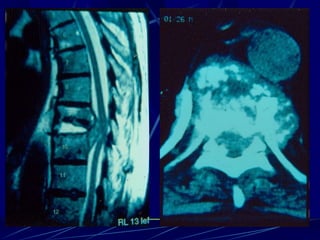

Epidural abscess

(Staphylococcus)